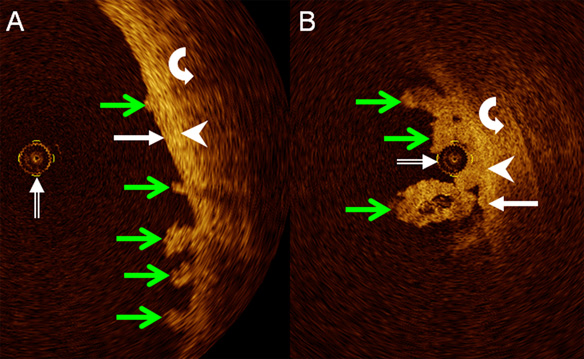

Catheter-based intraluminal optical coherence tomography of the normal human upper urinary tract in vivo: proof of concept and comparison with an ex-vivo porcine model

Ulrike L. Mueller-Lisse, Markus Bader, Elisabeth Englram, Christian Stief, Maximilian F. Reiser, Ullrich G. Mueller-Lisse